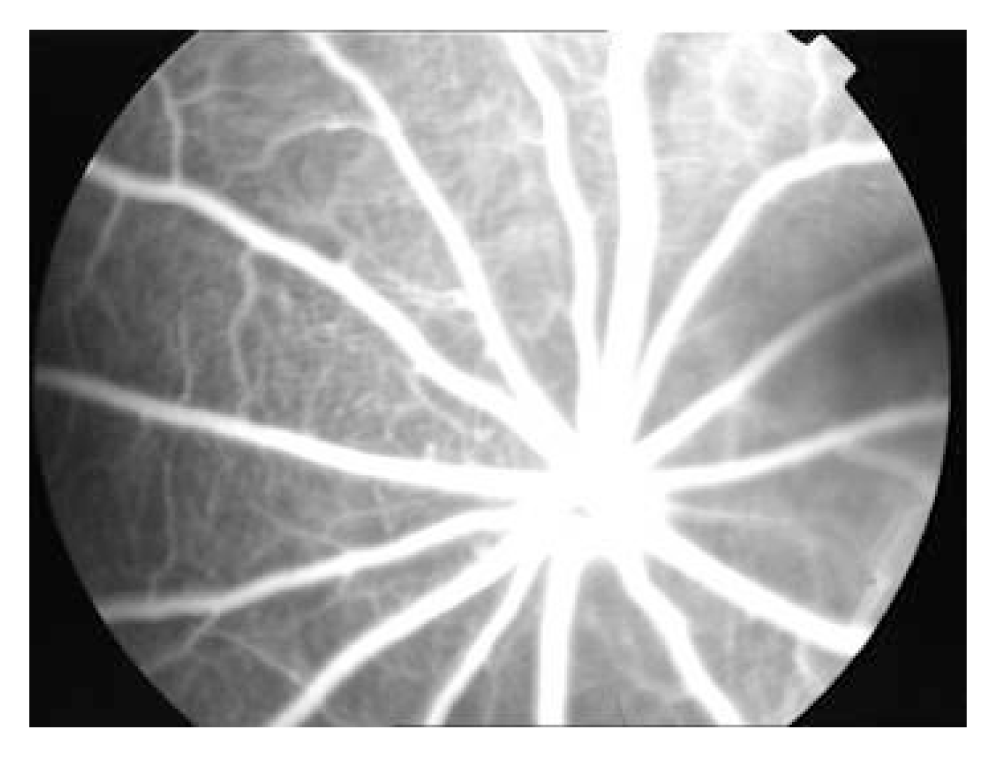

Figure 1.

At day 7 after photocoagulation, FFA showed that A. laser injury group: mild fluorescein leakage was seen in laser spots of BN rats; B. endostatin group I: 2 laser spots with mild leakage can be seen; C. endostatin group II: no apparent fluorescein leakage was observed.